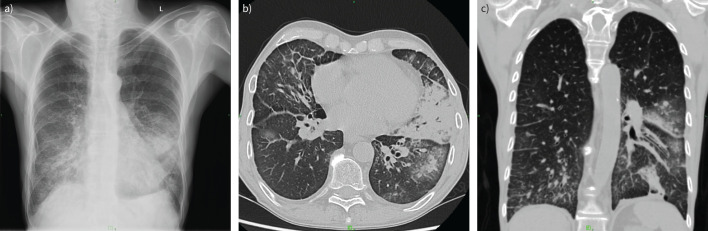

Imaging methods are fundamental tools to detect and diagnose lung diseases, monitor their treatment and detect possible complications. Each modality, starting from classical chest radiographs and computed tomography, as well as the ever more popular and easily available thoracic ultrasound, magnetic resonance imaging and nuclear medicine methods, and new techniques such as photon counting computed tomography, radiomics and application of artificial intelligence, has its strong and weak points, which we should be familiar with to properly choose between the methods and interpret their results. In this review, we present the indications, strengths and main limitations of methods for chest imaging.